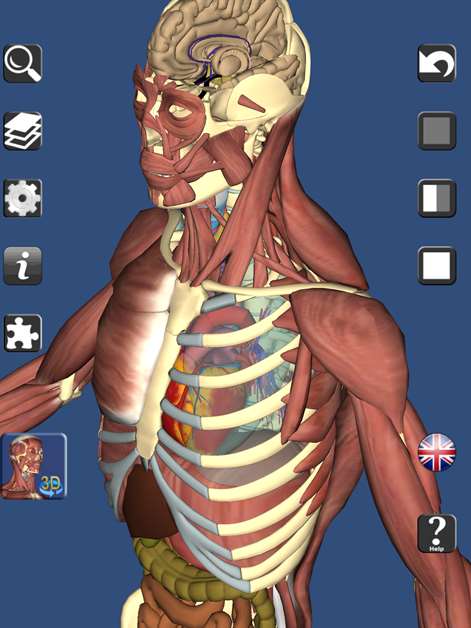

A true and totally 3D free app for learning human anatomy with position quiz, built on an advanced interactive 3D touch interface. It is completely free! (No in-app purchase). It has every bone and organ in the human body. ***From the creator of Visual Anatomy app

Features: ★ You can rotate models to any angle and zoom in and out ★ Easy to navigate and explore human body ★ Virtual dissection: Peel layers of muscles and reveal the anatomical structures below them. ★ 3D location quizzes to test your knowledge ★ Switch on/off different anatomy systems ★ Information from Wikipedia and Gray's anatomy textbook ★ Great for learning anatomy and physiology ★ It also can be used as a anatomy guide. ★ Support French, Spanish and German languages! ★ Audio pronunciation for all bone names Contents: ★ 3D Skeleton (all bones in our body) ★ 3D Ligaments (shoulder and knee ligaments only) ★ 3D Muscles (Upper body muscles) ★ 3D Respiratory system ★ Circulation (heart) ★ Nervous System (brain) ★ 3D Reproductive system (male and Female) ★ 3D Urinary system �� 3D ear